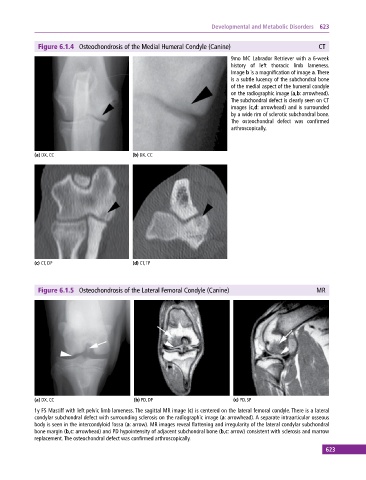

Figure 6.1.4 Osteochondrosis of the Medial Humeral Condyle (Canine) CT

9mo MC Labrador Retriever with a 6‐week

history of left thoracic limb lameness.

Image b is a magnification of image a. There

is a subtle lucency of the subchondral bone

of the medial aspect of the humeral condyle

on the radiographic image (a,b: arrowhead).

The subchondral defect is clearly seen on CT

images (c,d: arrowhead) and is surrounded

by a wide rim of sclerotic subchondral bone.

The osteochondral defect was confirmed

arthroscopically.

(a) DX, CC (b) DX, CC

(c) CT, DP (d) CT, TP

Figure 6.1.5 Osteochondrosis of the Lateral Femoral Condyle (Canine) MR

(a) DX, CC (b) PD, DP (c) PD, SP

1y FS Mastiff with left pelvic limb lameness. The sagittal MR image (c) is centered on the lateral femoral condyle. There is a lateral

condylar subchondral defect with surrounding sclerosis on the radiographic image (a: arrowhead). A separate intraarticular osseous

body is seen in the intercondyloid fossa (a: arrow). MR images reveal flattening and irregularity of the lateral condylar subchondral

bone margin (b,c: arrowhead) and PD hypointensity of adjacent subchondral bone (b,c: arrow) consistent with sclerosis and marrow

replacement. The osteochondral defect was confirmed arthroscopically.